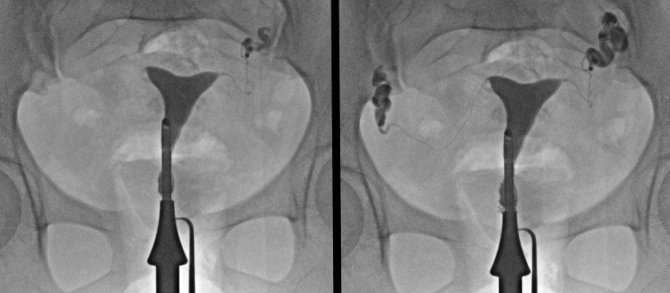

Histerosalpingografi (HSG) olarak isimlendirilen rahim filmi, bebeğin gelişimini tamamladığı rahim yani uterus boşluğu endometrium ile yumurtanın rahime taşındığı tüplerin görüntülenmesini sağlıyor.

HSG ile rahmin kalıtsal sorunları, miyom veya polip gibi kitleleri, düşük, kürtaj veya enfeksiyon gibi nedenlerle olaşabilecek yapışıklıklar ile birlikte tüplerde darlık, tıkanıklık veya genişleme gibi sorunların tespit edildiğini ifade eden Doruk Sağlık Grubu Yıldırım Hastanesi Grişimsel Radyoloji uzmanı Doç. Dr. Nurullah Doğan, "HSG en çok kısırlık veya düşük durumlarında kadın hastalıkları ve doğum uzmanı tarafından istenir. Daha önce kullanılan yöntemlerin hiç biri HSG'nin verdiği bilgilerin tamamını veremez" diye konuştu.

İşlem rahim ağzında verilen ilacın rahim boşluğu ve tüpleri doldurması sonucu şeklinde uygulandığını ifade eden Doç. Dr. Nurullah Doğan, "Elde edilen radyolojik görüntüler incelenerek teşhis konulur. Verilen ilaç renksiz ve kokusuz olup organ ve dokular üzerinde bir zararı yoktur. Tetkik için rahmin en uygun olduğu zaman adet bitiminden sonraki 3 ve 7 inci günler arasıdır. Hasta işlem sonrası aynı gün içinde normal yaşamına dönebilir. Utanma veya korku gibi sebeplerde ise isteyen hastalarda işlem hafif ve kısa süreli bir anestezi yani sedasyon altında yapılabilir. Gebelik, pelvik enfeksiyon, aşırı kanama ve yakın zamanda yapılan uterus veya tüpler ile ilgili ameliyat olması durumu HSG işlemi yapılmaz. HSG sadece teşhis koyulmasını sağlayan değil, bazı hastalarda tedavi edici bir işlemdir. Yüksek basınçla verilen kontrast madde tüplerdeki mukus benzeri engelleyici yapıları temizler. Bu sebeple kısırlık gelişen hastalarda tüplerin temizlenmesi sonrası yumurtalar rahim boşluğuna ulaşarak gebelik sağlanır" dedi.